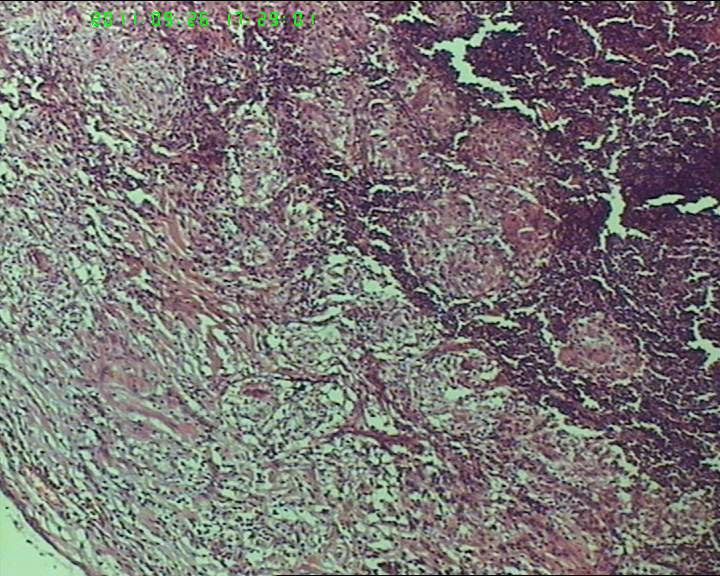

灰白不整形肿物一个,大小3.5*2.5*2cm,包膜完整。

21岁女性左侧颌下淋巴结,该诊断什么?图1

慢性肉芽肿性炎症,形态学倾向结节病,但是作为病理工作者对于这样的病例,再结合咋们国情,还是建议临床除外增殖性结核后再考虑结节病。